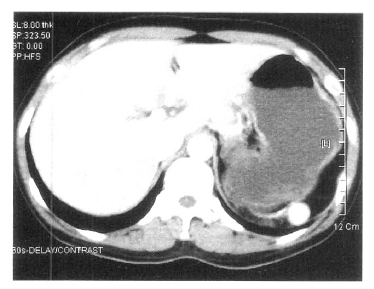

A 37-year-old woman was admitted to our hospital due to gum bleeding and petechiae in both lower extremities for three days. She had a known diagnosis of AITP and had undergone a splenectomy 11 years ago. She denied taking any medications prior to this hospitalization. On admission, her temperature was 36.6°C and her blood pressure was 110/70 mmHg. The physical examination was unremarkable except for the oozing of blood in oral cavity and a diffuse petechiae in both lower extremities. A splenectomy scar was present in her abdomen. The WBC was 7,200/mm3, hemoglobin was 12.4 g/dL, and platelet count was 3,000/mm3. The serum electrolytes and liver chemistry were within normal limits. Serum urea nitrogen and creatinine were normal. A routine urine analysis showed the presence of microscopic hematuria. The coagulation profile was all within the normal limits. Daily prednisolone and intravenous immunoglobulin (IVIG) were started. A spleen scan obtained after the intravenous injection of technetium-99m-labeled denatured RBC revealed a focal uptake in the posterior aspect of the left upper quadrant, and these findings are consistent with the presence of an accessory spleen (Figure 1). A computed tomographic (CT) scan of the abdomen revealed a 2×2 cm sized soft tissue lesion on the left sub-diaphragmatic area (Figure 2). On the 22nd hospital day, an accessory splenectomy was performed and the operation proceeded without complication. A dark brown mass was obtained and the pathologic finding was splenic tissue (Figure 3). The postoperatively platelet count soon increased to 71,000/mm3 and the patient was discharged. Two months after the accessory splenectomy, her platelet count dropped to 5,000/mm3. A repeated follow-up spleen scan did not show any remaining accessory spleen. A bone marrow examination showed there was still adequate megakaryocytes with normal hematopoiesis (Figure 4). She is being managed with oral cyclophosphamide with a stable platelet count in the range of 50000/mm3 at present.